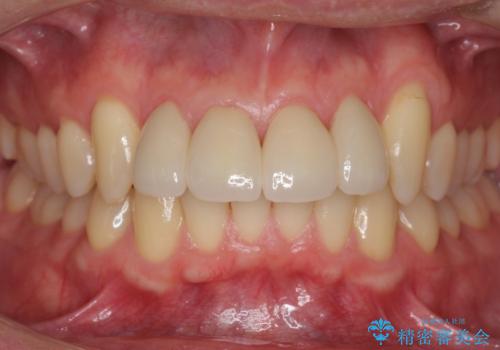

矯正治療か、セラミックで最短で治すかの選択肢を提示し、セラミックで治すことにしました。

利点は、早く終わる上に、保定の必要がないため負担が少ないことが挙げられます。

- 51.7万円 (ジルコニアクラウン スタンダード11万円x4本、仮歯1.1万円x4本、ナイトガード 3.3万円)税込費用は治療当時の料金となります

全て神経は取らずに、削りました。

長年コンプレックスだったすき間が閉じたとのことで、喜んでいただきました。